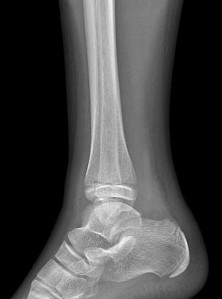

A 13-year-old girl sustains an ankle injury during a soccer match. Radiographs reveal an isolated Salter-Harris III fracture of the anterolateral distal tibial epiphysis (Tillaux fracture). Which of the following describes the anatomical sequence of distal tibial physeal closure that predisposes adolescents to this specific fracture pattern?

Explanation